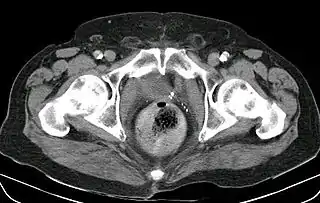

![]() Fecaloma rectal en un paciente hospitalizado. Presenta, además, una neovejiga y aterosclerosis. TC abdominal. | ||

Un fecaloma (llamado también fecalito y coprolito, i.e., piedras de heces), es una acumulación de heces en el recto o en el colon, que taponan el flujo normal del tracto intestinal.[1] A veces, están pegados a las paredes del intestino y puede ser causado por situaciones que enlentecen el tránsito intestinal: tercera edad, estreñimiento por deshidratación, enfermedad de Chagas, (por destrucción del sistema nervioso autónomo, enfermedad parasitaria propia de México, América Central y América del Sur), enfermedad de Hirschsprung, etc.